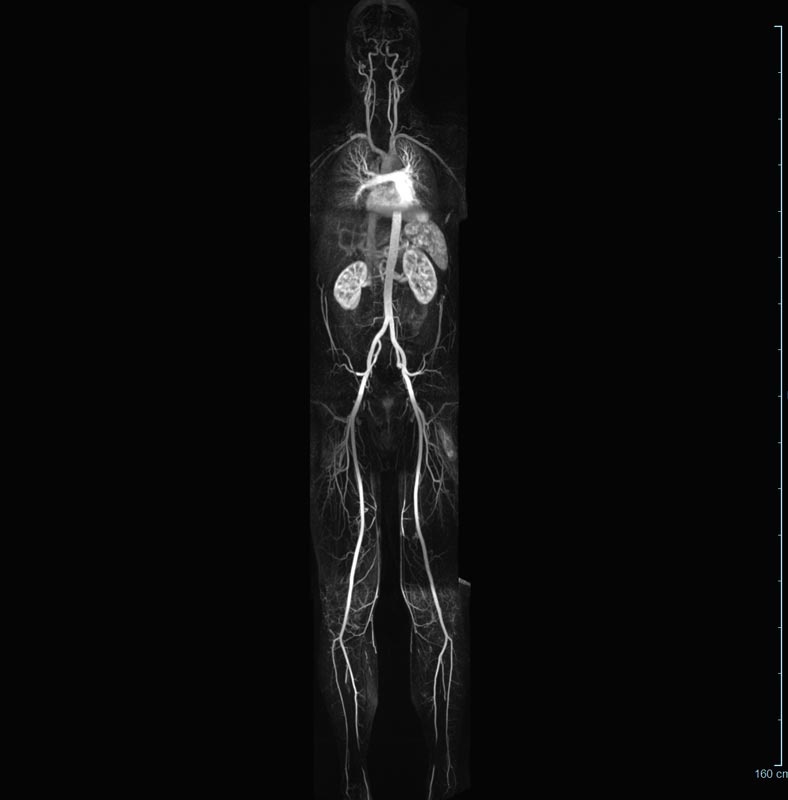

- Bauchgefäße

- Erfassung und Verlaufskontrolle bei arteriellen Aneurysmen (Aussackungen der Arterien), vor allem der Bauchaorta

- Darstellung von Gefäßengen an Nierenarterien, Baucharterien und Becken-/Beinarterien

- MR-Angiographie mit Kontrastmittel

- Erfassung arterieller und venöser Gefäße/Bypässe aller Körperregionen mit 3D-Rekonstruktion

- je nach klinischer Fragestellung zeitaufgelöste MR-Angiographie (4D-MRA) z.B. bei Frage arteriovenöse Fistel/ Shunt oder Darstellung Unterschenkelarterien vor geplanter Bypassoperation.